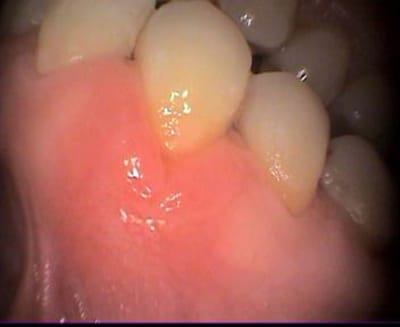

Cette patiente d'une soixantaine d'années présente depuis plusieurs semaine cette lésion en vestibulaire de 34.

Le sondage ne révèle pas de poche autour de la dent, à peine 3mm en vestibulaire. Peu de douleur au niveau gencive, en revanche mobilité de la 34, amplitude 1,5 mm.

Le reste de la bouche est nickel; l'hygiène impeccable.

La percussion commence à être douloureuse, enfin sensible.

Test au froid impossible, les voisines ne réagissant pas au test non plus.

je propose une résorption radiculaire externe.

Merci, il me semble aussi voir un trait de fracture à la courbure avant l'apex et une résorption externe en distal.